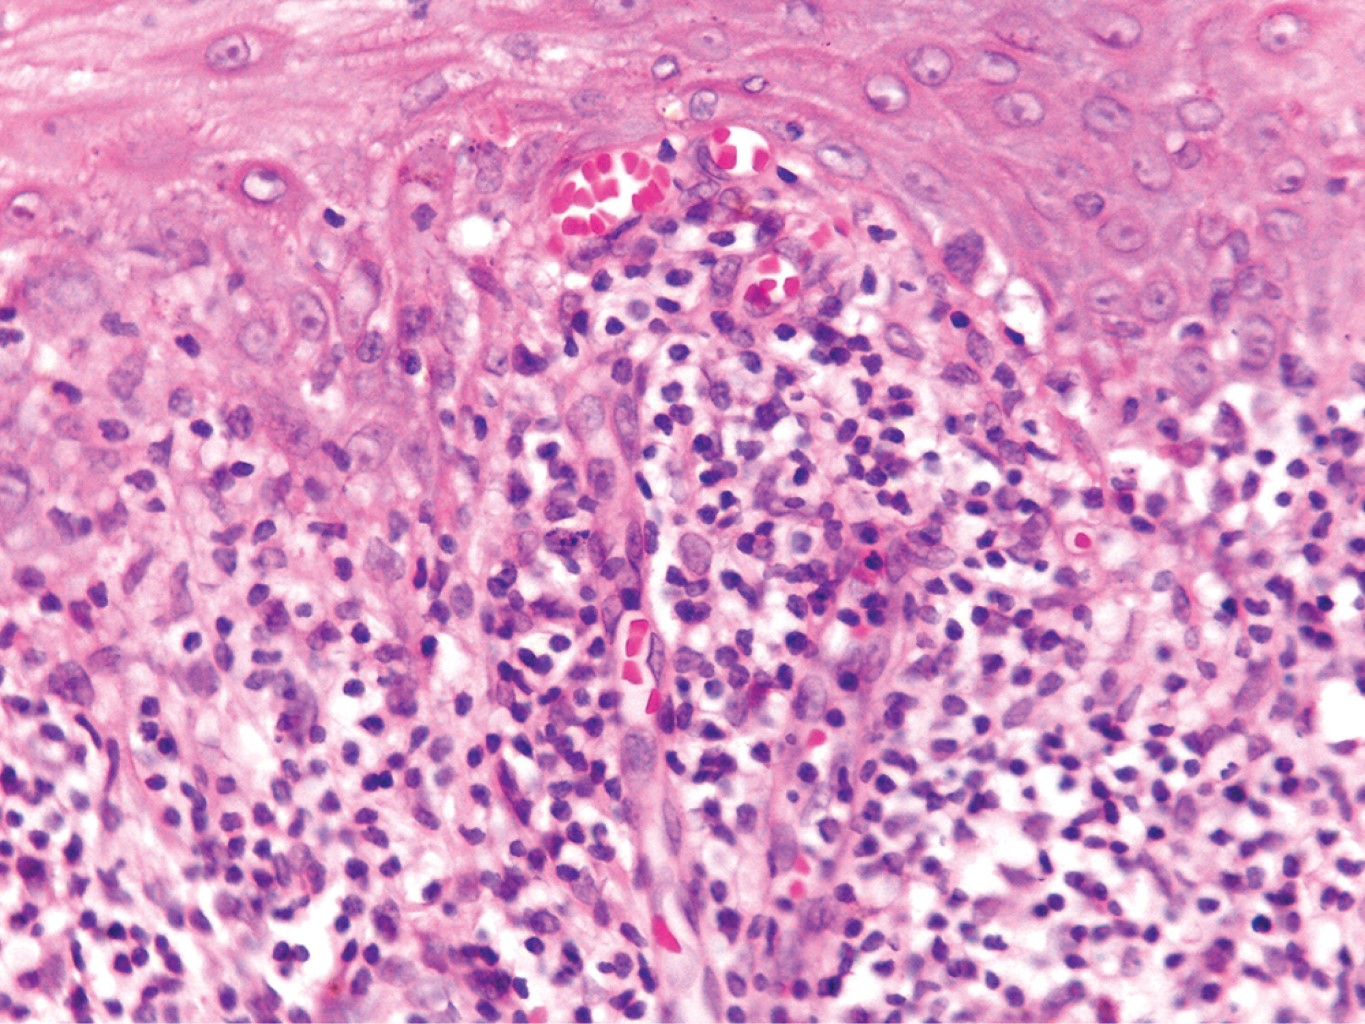

Se realizó biopsia incisional en una de las placas, la cual reportó epidermis con hiperqueratosis ortoqueratósica, tapones córneos, hipergranulosis focal, zonas con acantosis irregular moderada que alternan con áreas de atrofia y degeneración hidrópica de la capa basal con formación de cuerpos coloides; en dermis superficial vasos dilatados e infiltrado moderadamente denso dispuesto en banda constituido por linfocitos, histiocitos y algunos melanófagos (Figuras 2 y 3).

HISTOPATOLOGíA

La migración de las células T CD8+ activadas da como resultado la muerte de queratinocitos basales debido a los efectos combinados del interferón-gamma (IFN-γ), interleucina 6 (IL), factor estimulante de colonias de granulocitos-macrófagos (GM-CSF) y el factor de necrosis tumoral alfa (TNF-α). Las características histopatológicas típicas del liquen plano dependen de la interacción variable entre la degeneración y licuefacción de las células basales y la regeneración epidérmica irregular. El primer cambio identificable en el LP es la presencia de cuerpos coloides y la incontinencia del pigmento asociada. Los cuerpos coloides, citoides o cuerpos de Civatte son estructuras redondas u ovaladas, homogéneas, con eosinófilos identificables dentro del epitelio basal y la dermis papilar, muestran positividad con el ácido periódico de Schiff (PAS), resistente a la diastasa, y pueden identificarse dentro de las pápulas, piel perilesional e incluso piel aparentemente no afectada. En el ámbito ultraestructural, los cuerpos citoides están compuestos por agregados de filamentos de 6 a 8 nm de diámetro, constituidos por queratina, bien ubicados.8

Las características histopatológicas de una pápula antigua son: hiperqueratosis, hipergranulosis en forma de cuña (que se manifiesta clínicamente como estrías de Wickham) relacionadas con los componentes intraepidérmicos de los conductos sudoríparos y los folículos pilosos, y acantosis irregular. Ésta a menudo tiene apariencia en "dientes de sierra". En ocasiones se pueden observar linfocitos e histiocitos en la epidermis, y ocasionalmente necrosis de células satélite, lo cual es característico del padecimiento, así como la degeneración y licuefacción de la capa basal del epitelio. Suelen observarse hendiduras subepidérmicas (espacios de Max Joseph). La incontinencia del pigmento también es frecuente. La dermis superior se encuentra ocupada por infiltrado linfo-histiocitario en banda, lo cual oscurece la unión dérmica-epidérmica. Es posible ver eosinófilos. La hiperqueratosis persiste aun cuando el LP ha remitido y la acantosis retrocede, dando una imagen de aplanamiento de la epidermis. En esta fase, puede haber cicatrices focales y el infiltrado dérmico es menos visible. Las lesiones pueden volverse completamente atróficas con un número variable de cuerpos coloides e incontinencia del pigmento, casi sin inflamación. Si hay escasos cuerpos coloides, la diferencia con la poiquilodermia puede ser muy difícil. En las lesiones de liquen plano anular, las características histológicas típicas sólo se ven en la periferia, en el borde activo de las lesiones.8